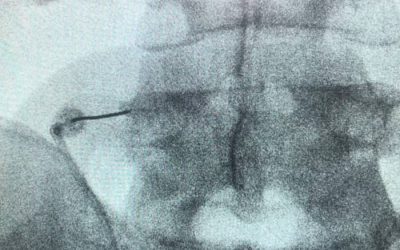

Bloqueo caudal – Hiato sacro

Para el manejo de las hernias discales que se producen principalmente en la columna lumbar y mas frecuentemente en el segmento vertebral L5 S1 un tratamiento...